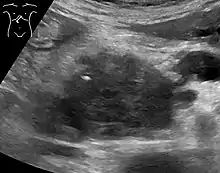

Medical imaging techniques, such as computed tomography (CT scan) and endoscopic ultrasound (EUS) are used both to confirm the diagnosis and to help decide whether the tumor can be surgically removed (its "resectability").[12] On contrast CT scan, pancreatic cancer typically shows a gradually increasing radiocontrast uptake, rather than a fast washout as seen in a normal pancreas or a delayed washout as seen in chronic pancreatitis.[55] Magnetic resonance imaging and positron emission tomography may also be used,[2] and magnetic resonance cholangiopancreatography may be useful in some cases.[31] Abdominal ultrasound is less sensitive and will miss small tumors, but can identify cancers that have spread to the liver and build-up of fluid in the peritoneal cavity (ascites).[12] It may be used for a quick and cheap first examination before other techniques.[56]